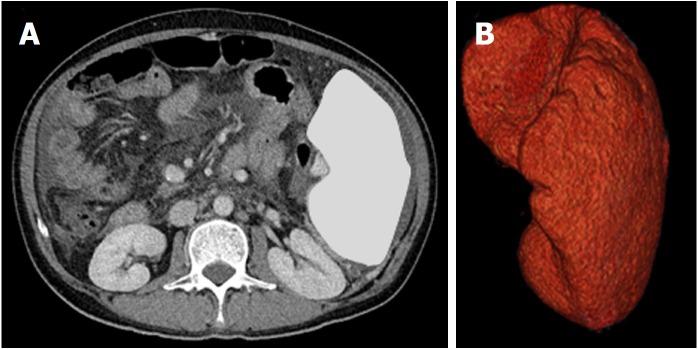

Relationship between response to lusutrombopag and splenic volume.

The numbers of responders and non-responders were 40 (80.0%) and 10 (20.0%), respectively. The patients were divided into a responder and non-responder group, and we added factors that may correspond to successful treatment with lusutrombopag. Splenic volume and body weight were lower in the responder group than in the non-responder group. White blood cell count and hemoglobin level were higher in responders compared with non-responders. Using a logistic regression model to assess the relationship between response to lusutrombopag and clinical characteristics, multivariate analysis confirmed that splenic volume was an independent factor that predicted the response of platelet counts ( = 0.025; odds ratio = 11.2; 95% confidence interval: 1.354-103.0). Splenic volume negatively correlated to changes in platelet count ( = -0.524, = 0.001).

Splenic volume influences the change in platelet counts after administration of lusutrombopag in patients with chronic liver disease.